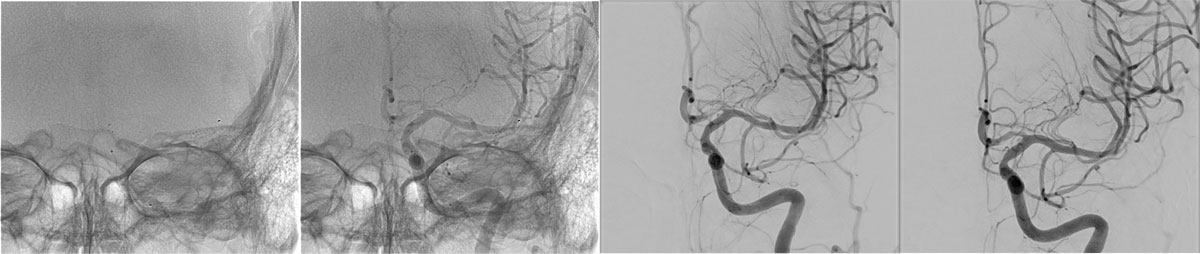

DSA

• BOBBY™ Balloon Guide Catheter

• Select-Sim

• Inflate the balloon, in order to dilate the true lumen

• MCA access with the softest system possible

• Open a stentriever for 20 mins with antiplatelet infusion

• Resheath the stentriever, check patency, if not stent-deployment

Headway™ DUO 156cm / Traxcess™ 14

CatchViewMini20

pEGASUS 4x20mm

VASO-CT post